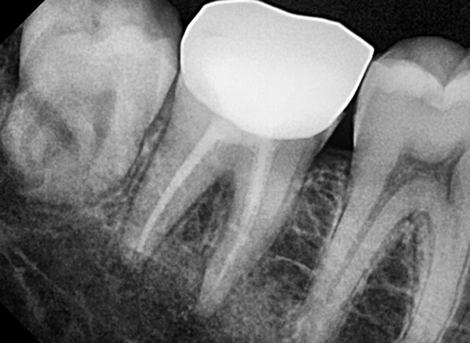

Cleaning & Filling

Laser Cleaning